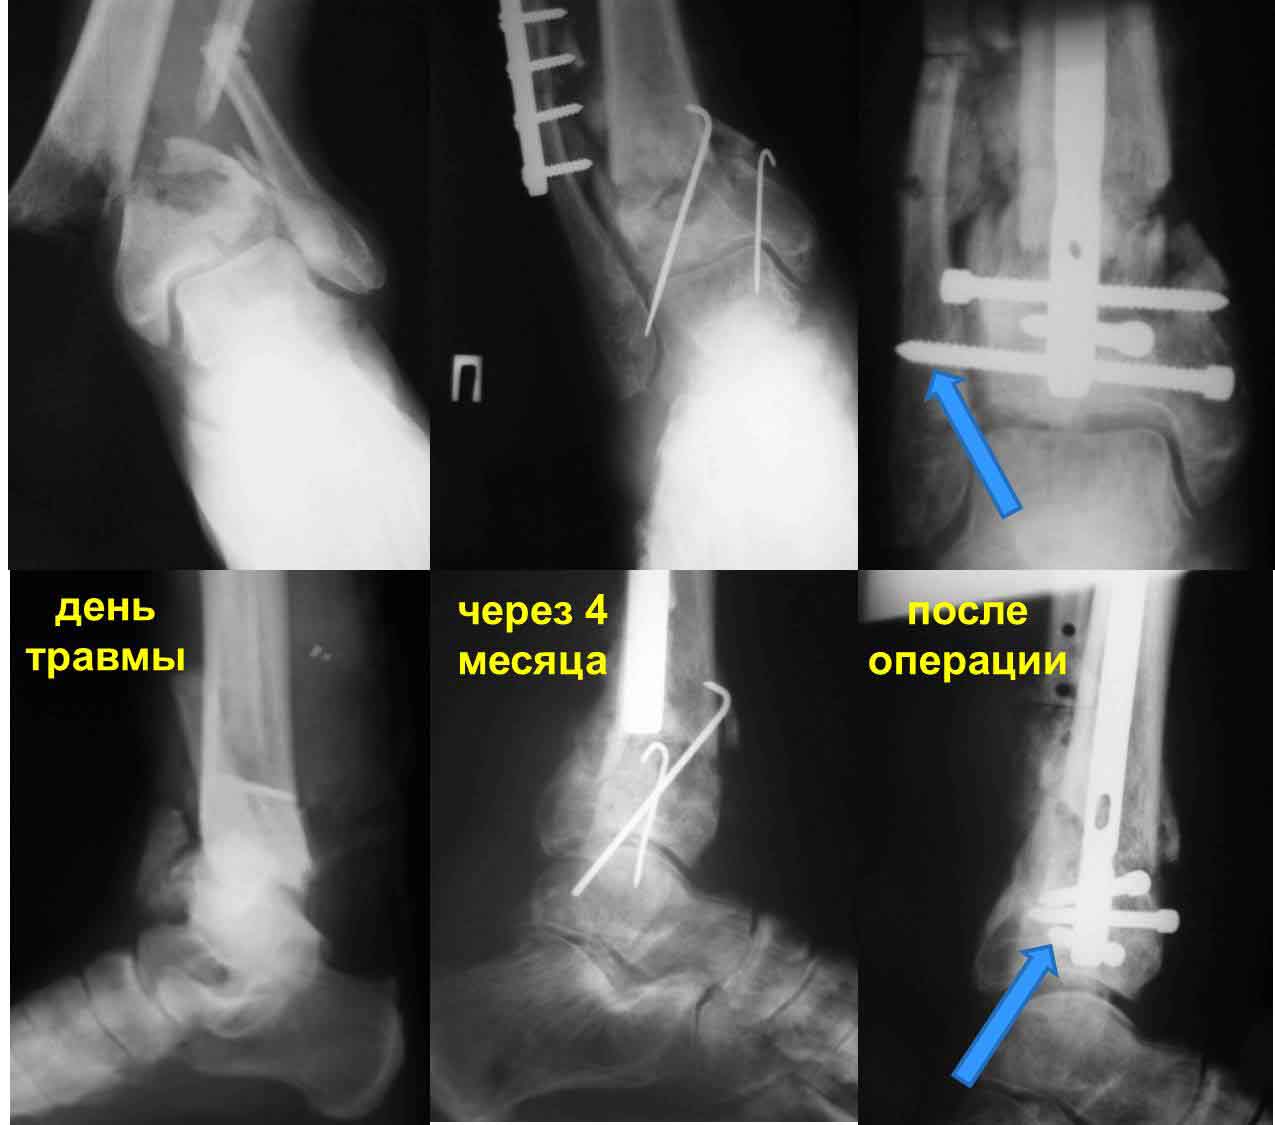

Частота ложных суставов и повторных смещений костных отломков после оперативной стабилизации переломов пилона доходит до 30%. Каждый, кто занимается лечением таких повреждений, наверняка сталкивался с такими осложнениями. Однако лечить такие осложнения в моральном, да и в оперативном плане проще, чем свежие переломы пилона (особенно Ruedi III), поскольку к этому времени становится более или менее понятной судьба голеностопного сустава. Если в достаточной мере владеете блокированным остеосинтезом, то самым оптимальным вариантом, с моей точки зрения, будет следующий. С переднемедиального и латерального доступов выполнить поперечную остеотомию большеберцовой и малоберцовой костей в плоскости параллельной плоскости голеностопного сустава на расстоянии около 3 см от самого сустава. Это минимальное расстояние, которое позволит расположить три блокирующих винта стержня. Важен выбор самого стержня. В данном случае больше всего подходит стержень ChM, имеющий на дистальном конце помимо отверстий в сагиттальной и фронтальной плоскостях и отверстия под углом в 45 градусов, причём на минимальном расстоянии друг от друга. Остетомию и последующую репозицию костных отломков мы выполняем в репозиционном спицевом аппарате. Стержень антеградный. В данном случае не вижу никаких оснований в применении ретроградного стержня, проходящего через здоровый подтаранный и через голеностопный сустав с его до конца неопределённой функцией. Образовавшийся дефект по переднемедиальной поверхности должен быть заполнен костным трансплантатом. Пример похожего случая из нашей практики - в приложенном файле.

Дистальный фрагмент должен быть интересен только в плане его величины (которая регулируется уровнем остеотомии) и способности прочно удерживать блокирующие винты стержня. Безусловно, возникнут трудности при репозиции отломков после остеотомии. Критерий репозиции – проекция центра костномозгового канала проксимального отломка на середину суставной поверхности большеберцовой кости в обеих плоскостях при отсутствии угловых деформаций. И трудность не столько в репозиции, сколько в удержание отломков в репонированном положении на время введения, блокирования стержня и рентгенконтроля. Поэтому мы выполняем такие операции в репозиционном аппарате.

Уважаемый VlaD! А что значит синяя стрелка на Вашей презентации? Проведение одного блокирующего винта через обе кости это принципиальный момент операции?

Слайд взят из собственной презентации по лечению переломов пилона. При переломах пилона в большинстве случаев больше всего подвергается разрушению переднелатеральная и латеральная часть большеберцовой кости из-за вальгусной установки пяточной кости и флексии стопы во время травмы. Поэтому самый дистальный винт, который располагается во фронтальной плоскости, мы, путём ротации стержня, стараемся провести и в малоберцовую кость, чтобы конец блокирующего винта располагался в прочной кости и выполнял свою функцию. Не знаю, насколько это принципиально, но так как обе кости связаны между собой синдесмозом, наверное, в этом есть рациональное зерно.